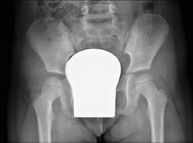

Procediment que permet, mitjançant l'ús de raigs X, i després d'injectar un contrast a l'interior de l'articulació, detectar lesions d'aquestes articulacions (cartílag, os, tendons, etc. ) segons la distribució del contrast. - RX Pelvis

Procediment que usa els raigs X a través de la qual s'obtenen imatges de la pelvis per al seu estudi, especialment dels ossos pèlvics. - RX Edat òssia